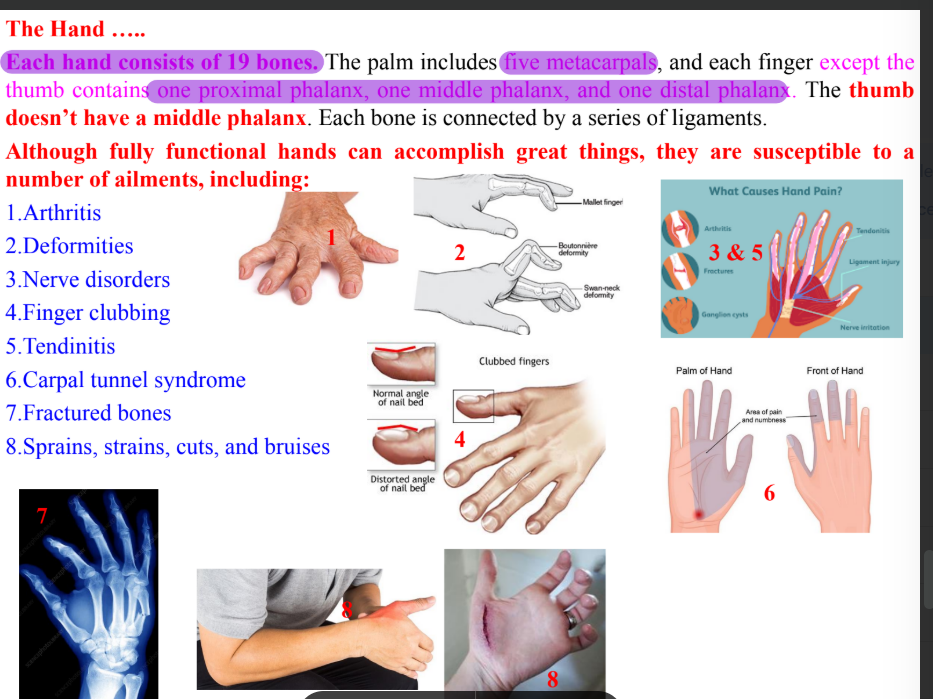

Clinical correlation of hand